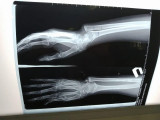

Шымкенттік дәрігерлер қисайған сүйекке алғаш рет ота жасады

Шымкент қалалық клиникалық балалар ауруханасының ортопед-травматологтары 14 жастағы қызға күрделі ортопедиялық ота жасады. Ота кезінде медицина мамандары жасөспірімнің қисық өскен шынтақ сүйегін хирургиялық жолмен қайта қалпына келтіріп берді. Балалар дәрігерлері мұндай отаны алғаш рет жасап, оң нәтижеге қол жеткізіп отыр, деп хабарлайды Egemen.kz.